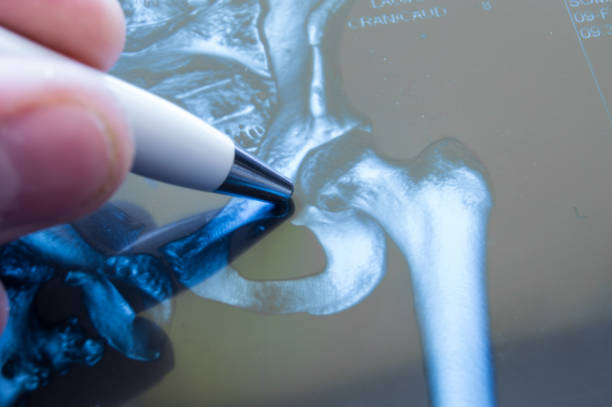

고관절 통증 원인-질환과 염증

고관절 통증은 다양한 질환과 염증으로 인해 발생할 수 있습니다. 관절염, 골관절염, 류마티스 관절염과 같은 질환은 고관절 통증을 유발하는 주요한 원인입니다. 또한 근육통, 건염, 인대염과 같은 염증도 고관절 통증을 초래할 수 있습니다. 이러한 질환과 염증은 적절한 치료와 관리가 필요하며, 통증이 계속되는 경우 전문의의 진단과 치료를 받아야 합니다.